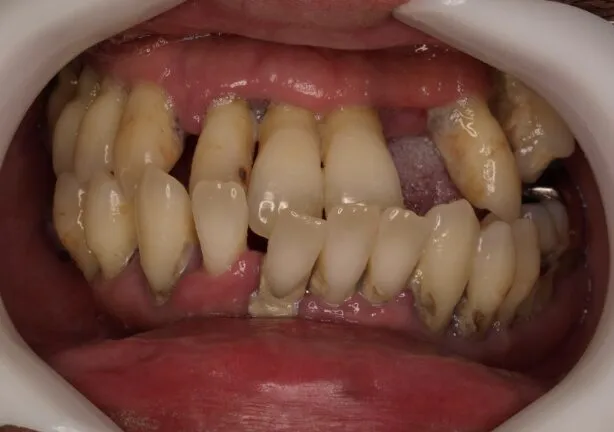

case2

Before

治療内容 | 口腔内診査〜カウンセリング 歯周初期治療 仮歯にて噛む位置の再設定 インプラント埋入 仮歯にてインプラントを含めた噛む位置の決定 最終的な被せ物(ジルコニア)の型取り〜装着 |

治療期間 | 1年半 |

治療回数 | 40回 |

リスク | リーニングにこない場合噛み合わせの確認ができないため装着していった人工物が割れてしまう可能性があるため、今後のメンテナンスが必須となる |

費用(税込) | 約¥2,860,000 |